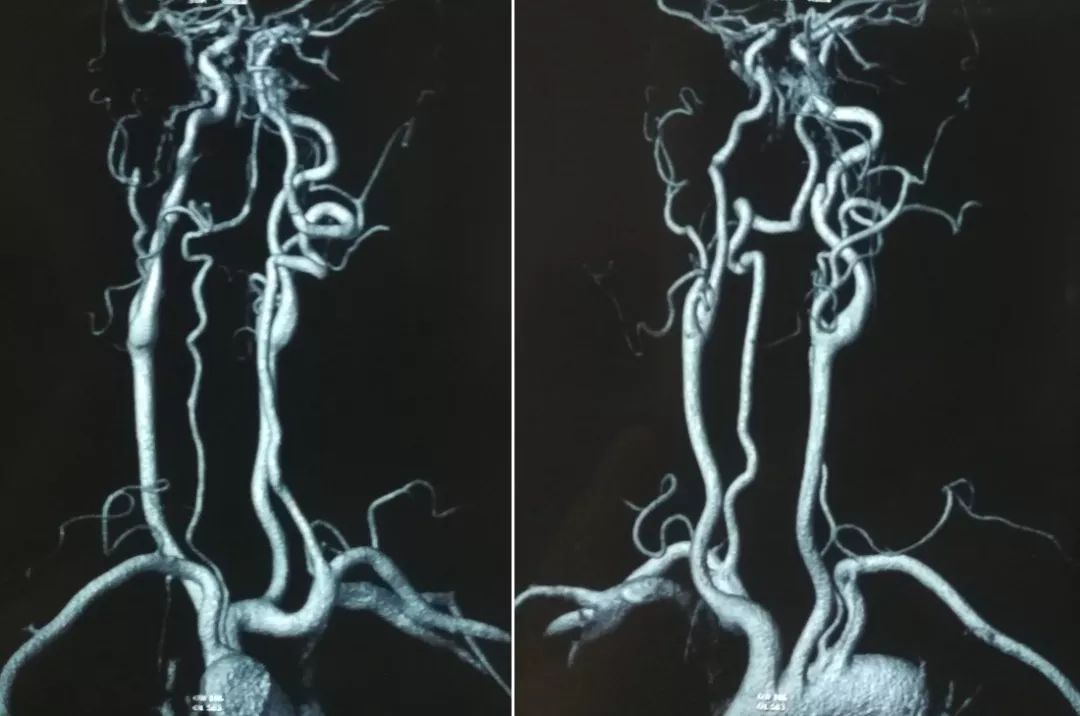

当地医院MRA检查(2019-9-9)(图3)

图3